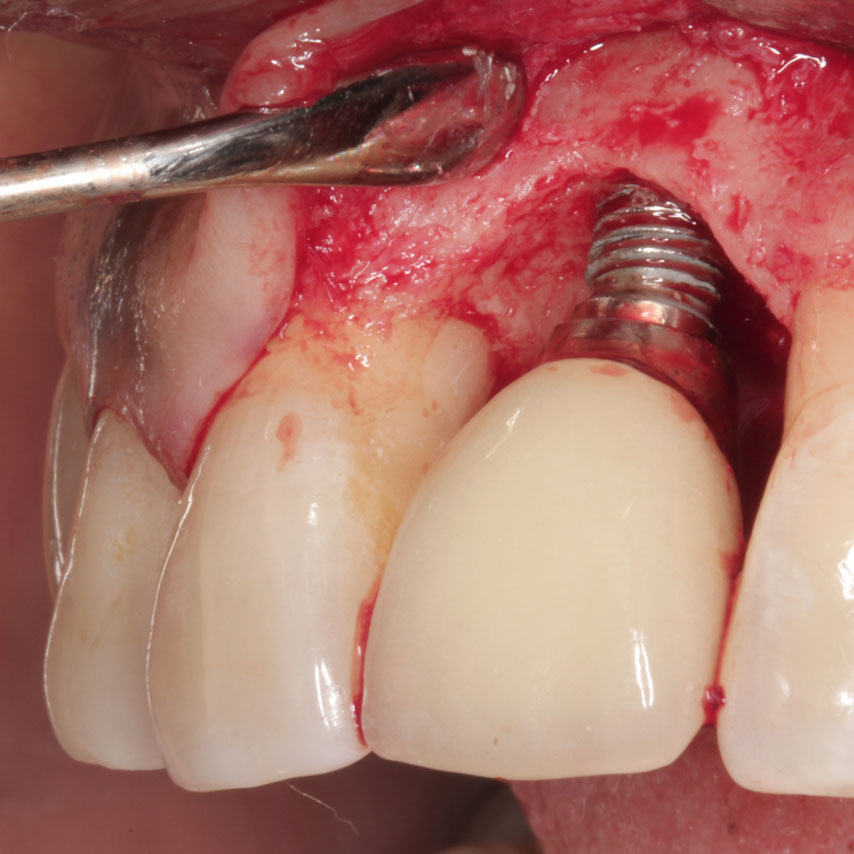

임플란트가 오랫동안

머물 수 있도록

한 번 잃어본 사람은 알죠. 지키지 못한 것이 얼마나 후회되는지..

디아트 테라피는 전체임플란트를 오랫동안 지키기 위한

'두 번째 보험'입니다.

한 번 심은 임플란트, 평생 쓸 수 있을까요?

해답은 '관리'에 있습니다

치주질환을 방치하면 뼈가 녹아내리며, 결국 발치에 이르게 됩니다. 잇몸이 무너진 후 치료는 더욱 어렵습니다.

임플란트에 가중되는 물리적인 힘(교합력)을 조절하고, 지속적으로 임플란트 주위염을 모니터링하면서, 전문가의 테크닉으로 그 원인을 안전하게 제거해야만, 전체 임플란트를 10년, 20년, 그리고 평생을 안정적으로 유지할 수 있습니다.

임플란트를 평생 지키기 위한, 단 하나의 선택

디아트 테라피로

임플란트 주위염을

예방합니다

임플란트를 오래 쓰기 위한 최선의 예방관리, 잇몸을 보호하고, 임플란트를 지킬 수 있는 맞춤형 솔루션입니다.

디아트 테라피는 전체임플란트를 오랫동안 지키기 위한 '두 번째 보험' 입니다.

해답은 ‘관리’에 있습니다

임플란트 주위염은 통증 없이 진행되다가, 어느 날 갑자기 임플란트가 흔들리며 발견되는 경우가 많습니다.

특히 전체임플란트처럼 여러 개의 식립체가 서로 구조적으로 연결되어 있는 경우, 염증이 하나에서 시작되어 연쇄적으로 확산될 수 있습니다.

임플란트에 가중되는 물리적인 힘(교합력)을 조절하고,

지속적으로 임플란트 주위염을 모니터링하면서,

전문가의 테크닉으로 그 원인을 안전하게 제거해야만,

전체 임플란트를 10년, 20년, 그리고 평생을 안정적으로 유지할 수 있습니다.

디아트 테라피로 임플란트 주위염을 예방합니다

임플란트를 오래 쓰기 위한 최선의 예방관리,

잇몸을 보호하고, 임플란트를 지킬 수 있는 맞춤형 솔루션입니다.